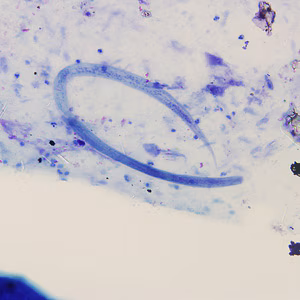

Strongyloides stercoralis third-stage filariform (L3) larvae.

Infective, third-stage filariform larvae (L3) of Strongyloides stercoralis are up to 600 µm long. The tail is notched and the esophagus to intestine ratio is 1:1, which helps distinguish it from hookworm filariform larvae (which have a short esophagus and pointed tail). Infective L3 larvae are found in soil and invade the human host by direct penetration of the skin. They may be found in respiratory specimens during cases of autoinfection.